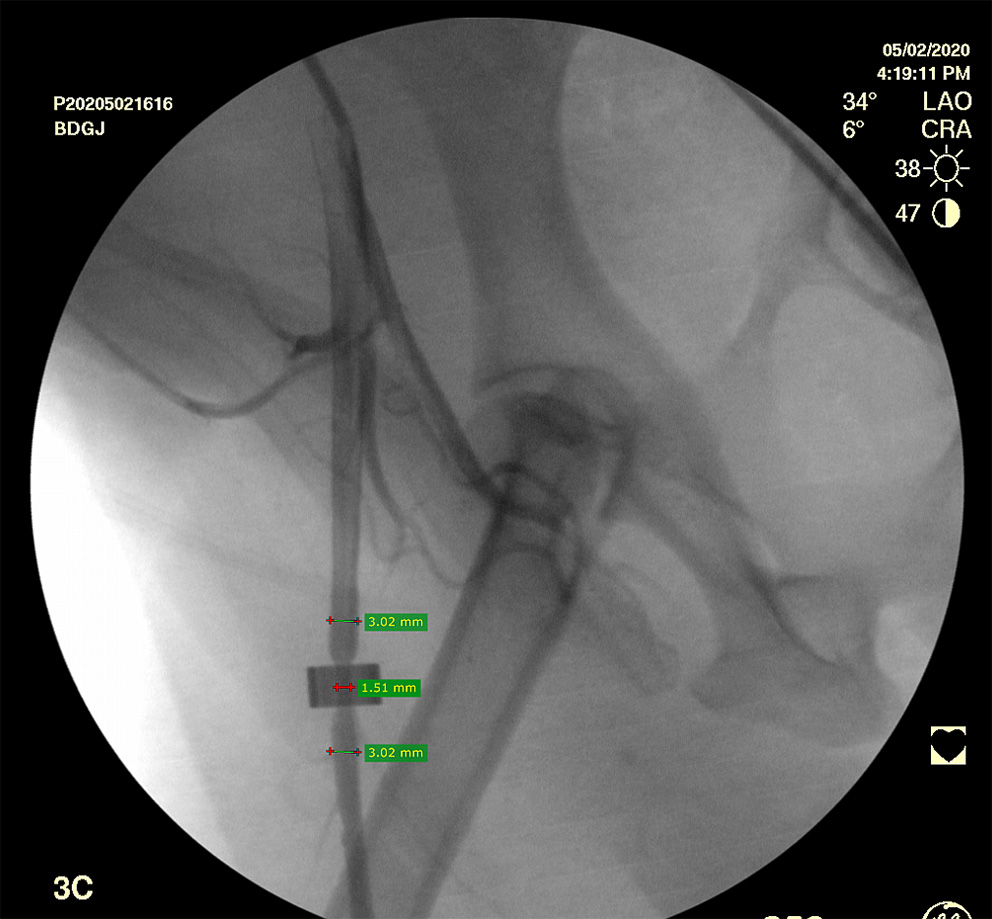

An arterial duplex ultrasound scan was performed 4–5 h after the surgery to exclude femoral artery spasm. A selective right femoral artery angiogram with was then performed with 2 perpendicular projections via left femoral artery catherization (OEC 9900 Elite mobile C-arm imaging system, GE Healthcare, USA). The establishment of the 50% canine femoral artery stenosis using the constrictor ring was confirmed when the angiogram demonstrated 50% stenosis (45–52%) (Figure 1).

Figure 1

Selective right femoral artery angiogram shows a canine femoral artery stenosis (50%).

Post-stenotic Tur indices recorded between 1 and 19 mm distal to a 50% stenosis following ameroid constrictor placement in 12 canine femoral arteries are shown in Table 2. The Tur index (>1) occurred in 83.3–100% of the cases between 1 and 9 mm distal to the stenosis. The number of cases with Tur index (>1%) decreased to 41.7–58.3% between 11 and 17 mm distal to the stenosis, and only 16.7% at 19 mm (Table 2 and Figure 3). Figure 4 shows Tur index changes in relation to distances distal to a 50% stenosis. Based on a canine femoral artery diameter of 3 mm, post-stenotic Tur index increased immediately distal to the stenosis and reached its maximum value at 5–11 mm or 1.7–3.7 diameters downstream in 9 of 12 cases (75%) with most at 7 mm or 2.3 times the vessel diameter downstream (5/12). The Tur index decreased sharply afterwards (Table 2 and Figure 4).